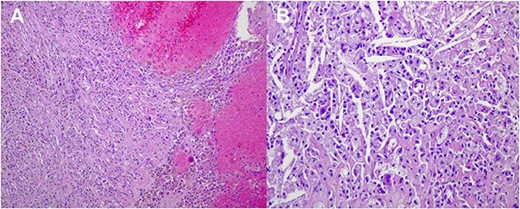

Histological images (20 × magnification) of the formalin-fixed paraffin-embedded sections. (A) shows no malignant cells and prominent interstitial hemorrhage with hemosiderin deposits due to treatment effect. (B) shows no malignant cells and numerous cholesterol clefts surrounded by foamy macrophages due to treatment effect.

On March 2023, the patient underwent left sided modified radical mastectomy with axillary lymph node dissection. Through an elliptical incision, the upper and lower flaps were dissected up to the upper and lower limits of breast tissue, the breast and pectoral fascia were excised. The axillary contents were removed after identifying the axillary vein, thoracodorsal and long thoracic nerves. The intercosto-brachial nerve was preserved. Homeostasis was secured. Red-i-vac drains were inserted. The skin was closed in -Y- shape duo to wide skin excision. The excised tissues were sent for histopathology. The patient was discharged in a good condition. Histopathology of excised tissue (shown in Fig. 7) showed fat necrosis, hemosiderin deposits, and giant cell reaction in keeping with treatment effect, but no evidence of residual malignancy. Sixteen lymph nodes were found, all free from malignancy, four of them showed fibrosis and hemosiderin deposits in keeping with treatment effect, marking complete pathological response.